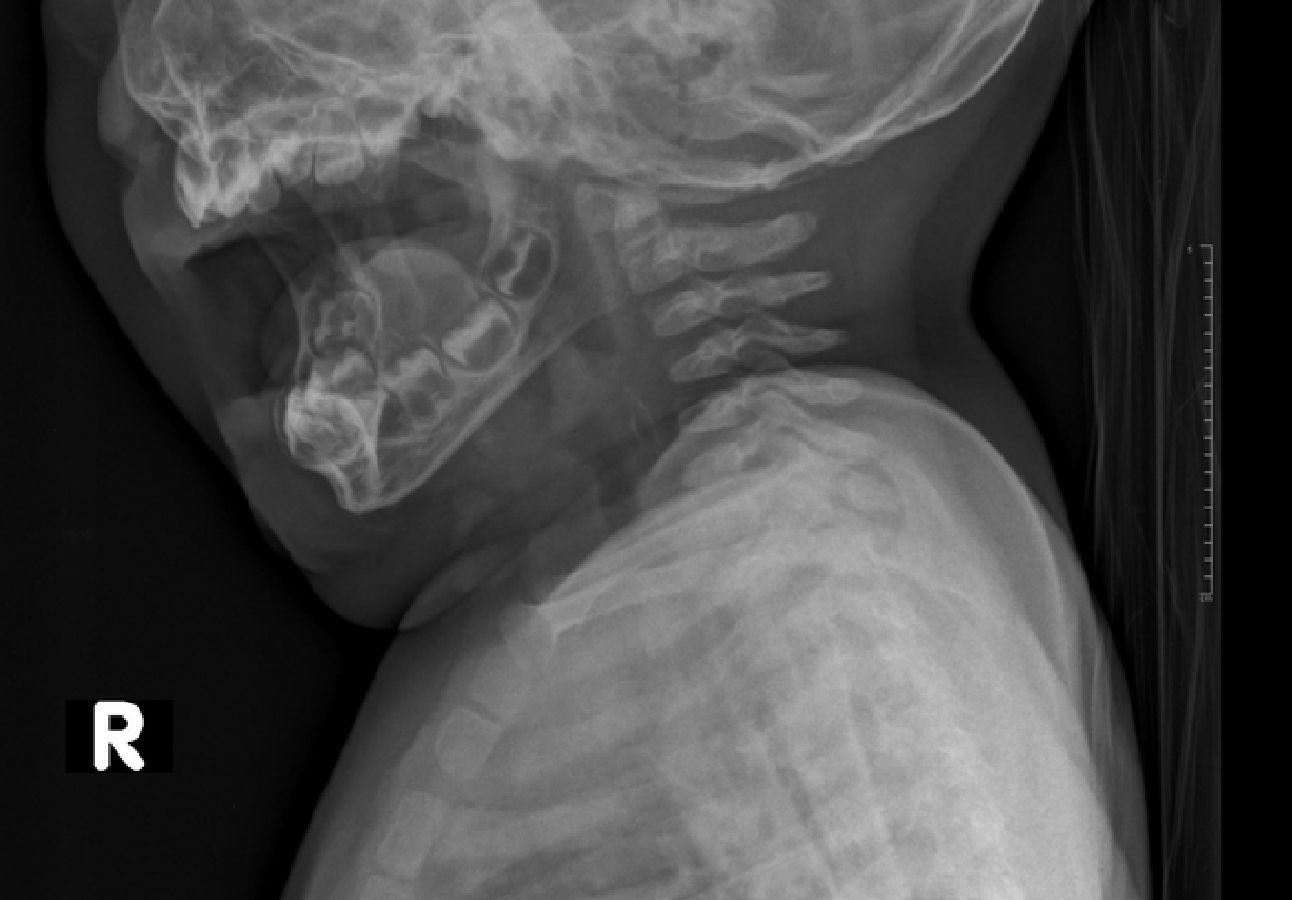

La niña se negó a beber porque estaba vomitando. Una investigación inicial no reveló nada, luego se detectó la calcomanía.

La niña se agita, vomita, babea y se niega a beber. Se hizo una radiografía y no mostró nada. La endoscopia reveló un cuerpo extraño: leemos en el perfil.